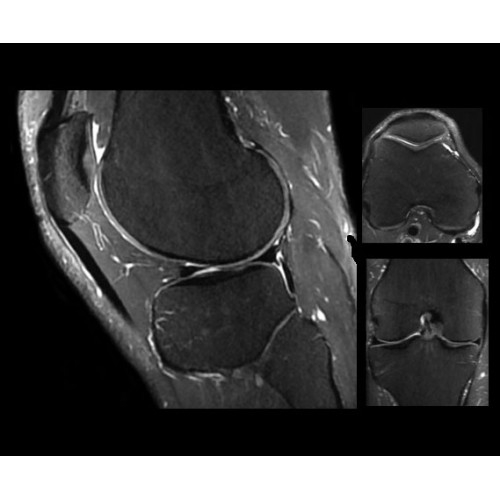

SIGNA PET/MR 3.0T — это гибридная система, в которой совмещаются две принципиально разные технологии — магнитно-резонансную томографию (МРТ) и позитронно-эмиссионную томографию (ПЭТ). Система отличающийся высокой чувствительностью и эффективностью и предназначена для диагностики в области онкологии, неврологии, кардио-васкулярных исследований, исследований воспалительных процессов.

Компания GE Healthcare представляет революционную, полностью интегрированную систему SIGNA PET/MR1, в которой сочетаются времяпролетная технология (TOF) и возможности напряженности магнитного поля 3.0 Тл. Мы поможем вам поднять исследования на более высокий уровень. SIGNA PET/MR позволяет достичь впечатляющей точности и скорости исследований, а благодаря новейшей технологии реконструкции Q.Clear2 качество изображений улучшается в два раза. Кроме того, в систему включен полный набор клинических приложений и гибких катушек для проведения любых видов исследования, открывая для вас возможности визуализации, о которых вы даже не догадывались.